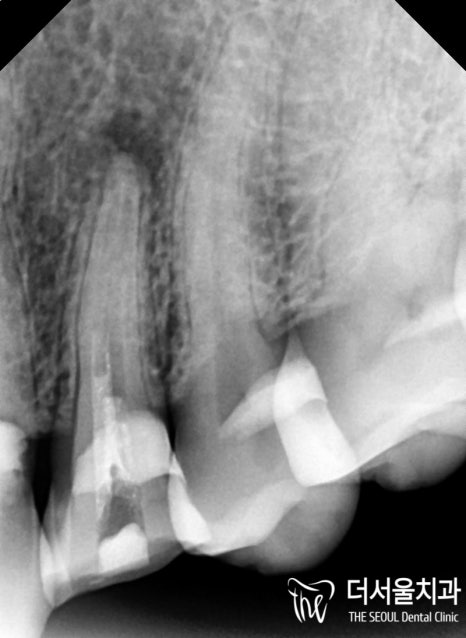

이때 개선을 도울 수 있는 방법으로는

신경치료 후 크라운 수복이 대표적인데요.

위 내용을 환자께 설명드린 후

자연치를 살리는 마지막 술식이

엔도를 진행하기로 했습니다.

신경치료 후 크라운 수복으로

개선을 돕기로 했기 때문에

내부에 감염된 병소들을

꼼꼼하게 제거하고

소독, 충전 과정을 거쳐

모든 과정을 마무리할 수 있었습니다.